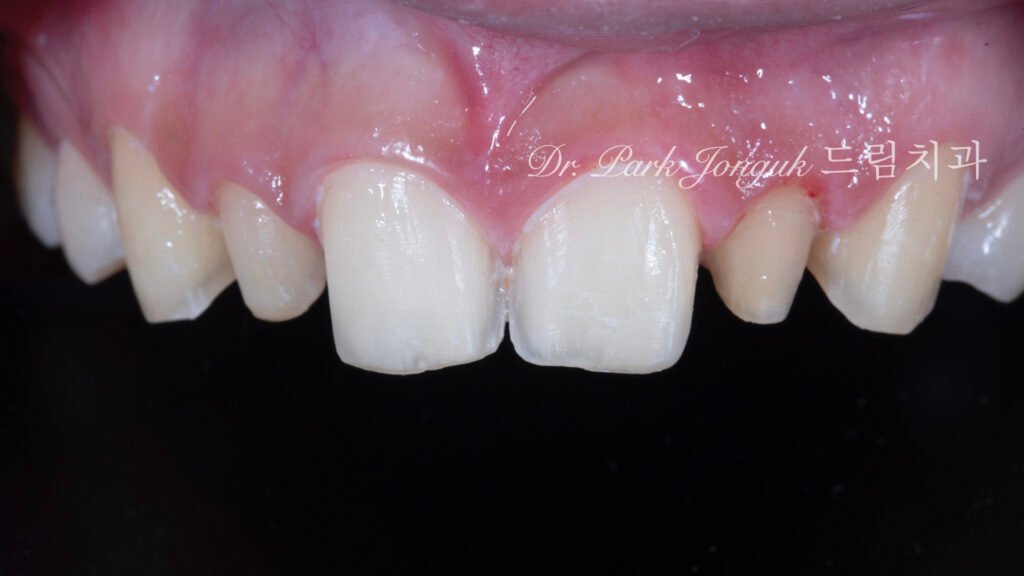

왜소측절치: 이미 과도하게 삭제된 상태였으므로 추가 치아 준비는 시행하지 않았습니다. 기존 치료의 과삭제는 매우 안타까운 부분이며, 이는 초기 치료 시 정밀 진단의 중요성을 다시 한번 강조합니다. 과삭제된 치아는 더 두꺼운 라미네이트가 필요하며, 이는 자연스러움을 저해할 수 있습니다.

중절치: 비대한 중절치의 크기를 줄이기 위해 표준보다 다소 많은 치아 준비가 필요했습니다. 비후된 치근으로 인해 치아 준비 자체의 난이도가 높았으며, 특히 치경부 윤곽을 자연스럽게 만드는 데 세심한 주의가 필요했습니다.

치경부 각도(cervical angle)는 치은에서 치아가 출현하는 모습을 결정하는 중요한 요소입니다. 비후 치근으로 인해 이 각도가 둔해지기 쉬운데, 이를 보정하기 위해 정밀한 형태 조정이 이루어졌습니다.

치아 간 비율: 왜소측절치는 정상 크기로 확대되었고, 비대했던 중절치는 적절한 크기로 축소되어 전체적으로 조화로운 비율이 만들어졌습니다. 중절치:측절치 비율이 생리학적 이상 범위에 도달하여, 더 이상 특정 치아가 유독 크거나 작아 보이지 않습니다.

비후 치근 문제의 해결: 중절치 치경부에 적용된 옐로우 스테인이 예상대로 작동했습니다. 굵은 치근으로 인한 두툼한 인상이 색상 그라데이션을 통해 자연스러운 뿌리 형태로 인식됩니다. 실제로 치근의 물리적 두께는 변하지 않았지만, 시각적으로는 자연 치아와 구별이 어려울 정도로 개선되었습니다.

심미적 통합: 전체적으로 인위적인 느낌 없이 자연스러운 치열로 보입니다. 치경부의 색상 변화, 표면의 미세한 질감, 적절한 투명도 등이 조화를 이루어 “라미네이트 했다”는 인식을 주지 않습니다.